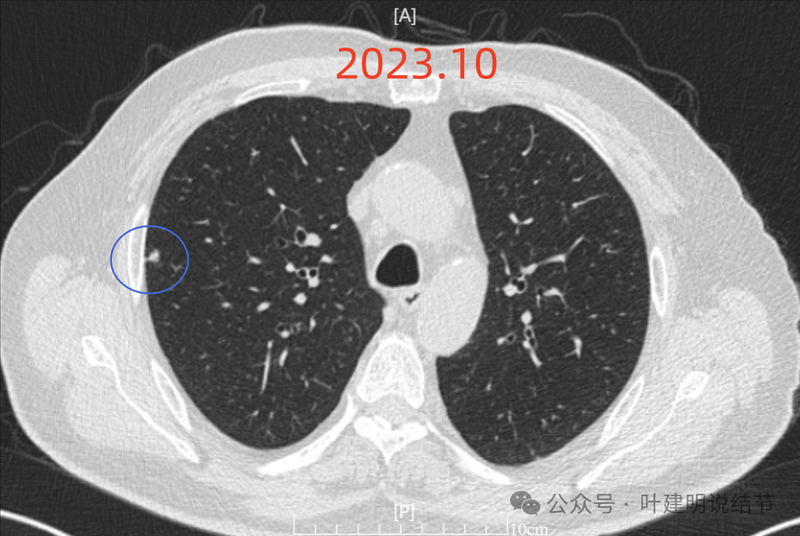

纵隔窗见为实性密度,同时见右侧纵隔腔静脉旁明显肿大淋巴结(蓝色箭头)。

回顾2023年右侧纵隔肿大淋巴结也是有的,而且大小与2024年9月的相仿。